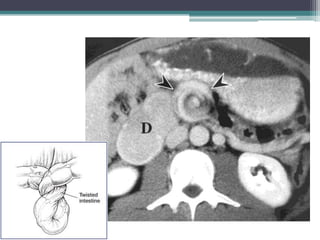

Tài liệu bàn về tắc ruột, bao gồm định nghĩa, phân loại và nguyên nhân của tình trạng này, với sự phân biệt giữa tắc cơ học và cơ năng. Các triệu chứng và chẩn đoán lâm sàng được trình bày, kèm theo phương pháp chẩn đoán cận lâm sàng như x-quang và siêu âm. Ngoài ra, tài liệu cũng đề cập đến các biến chứng và hậu quả của tắc ruột.